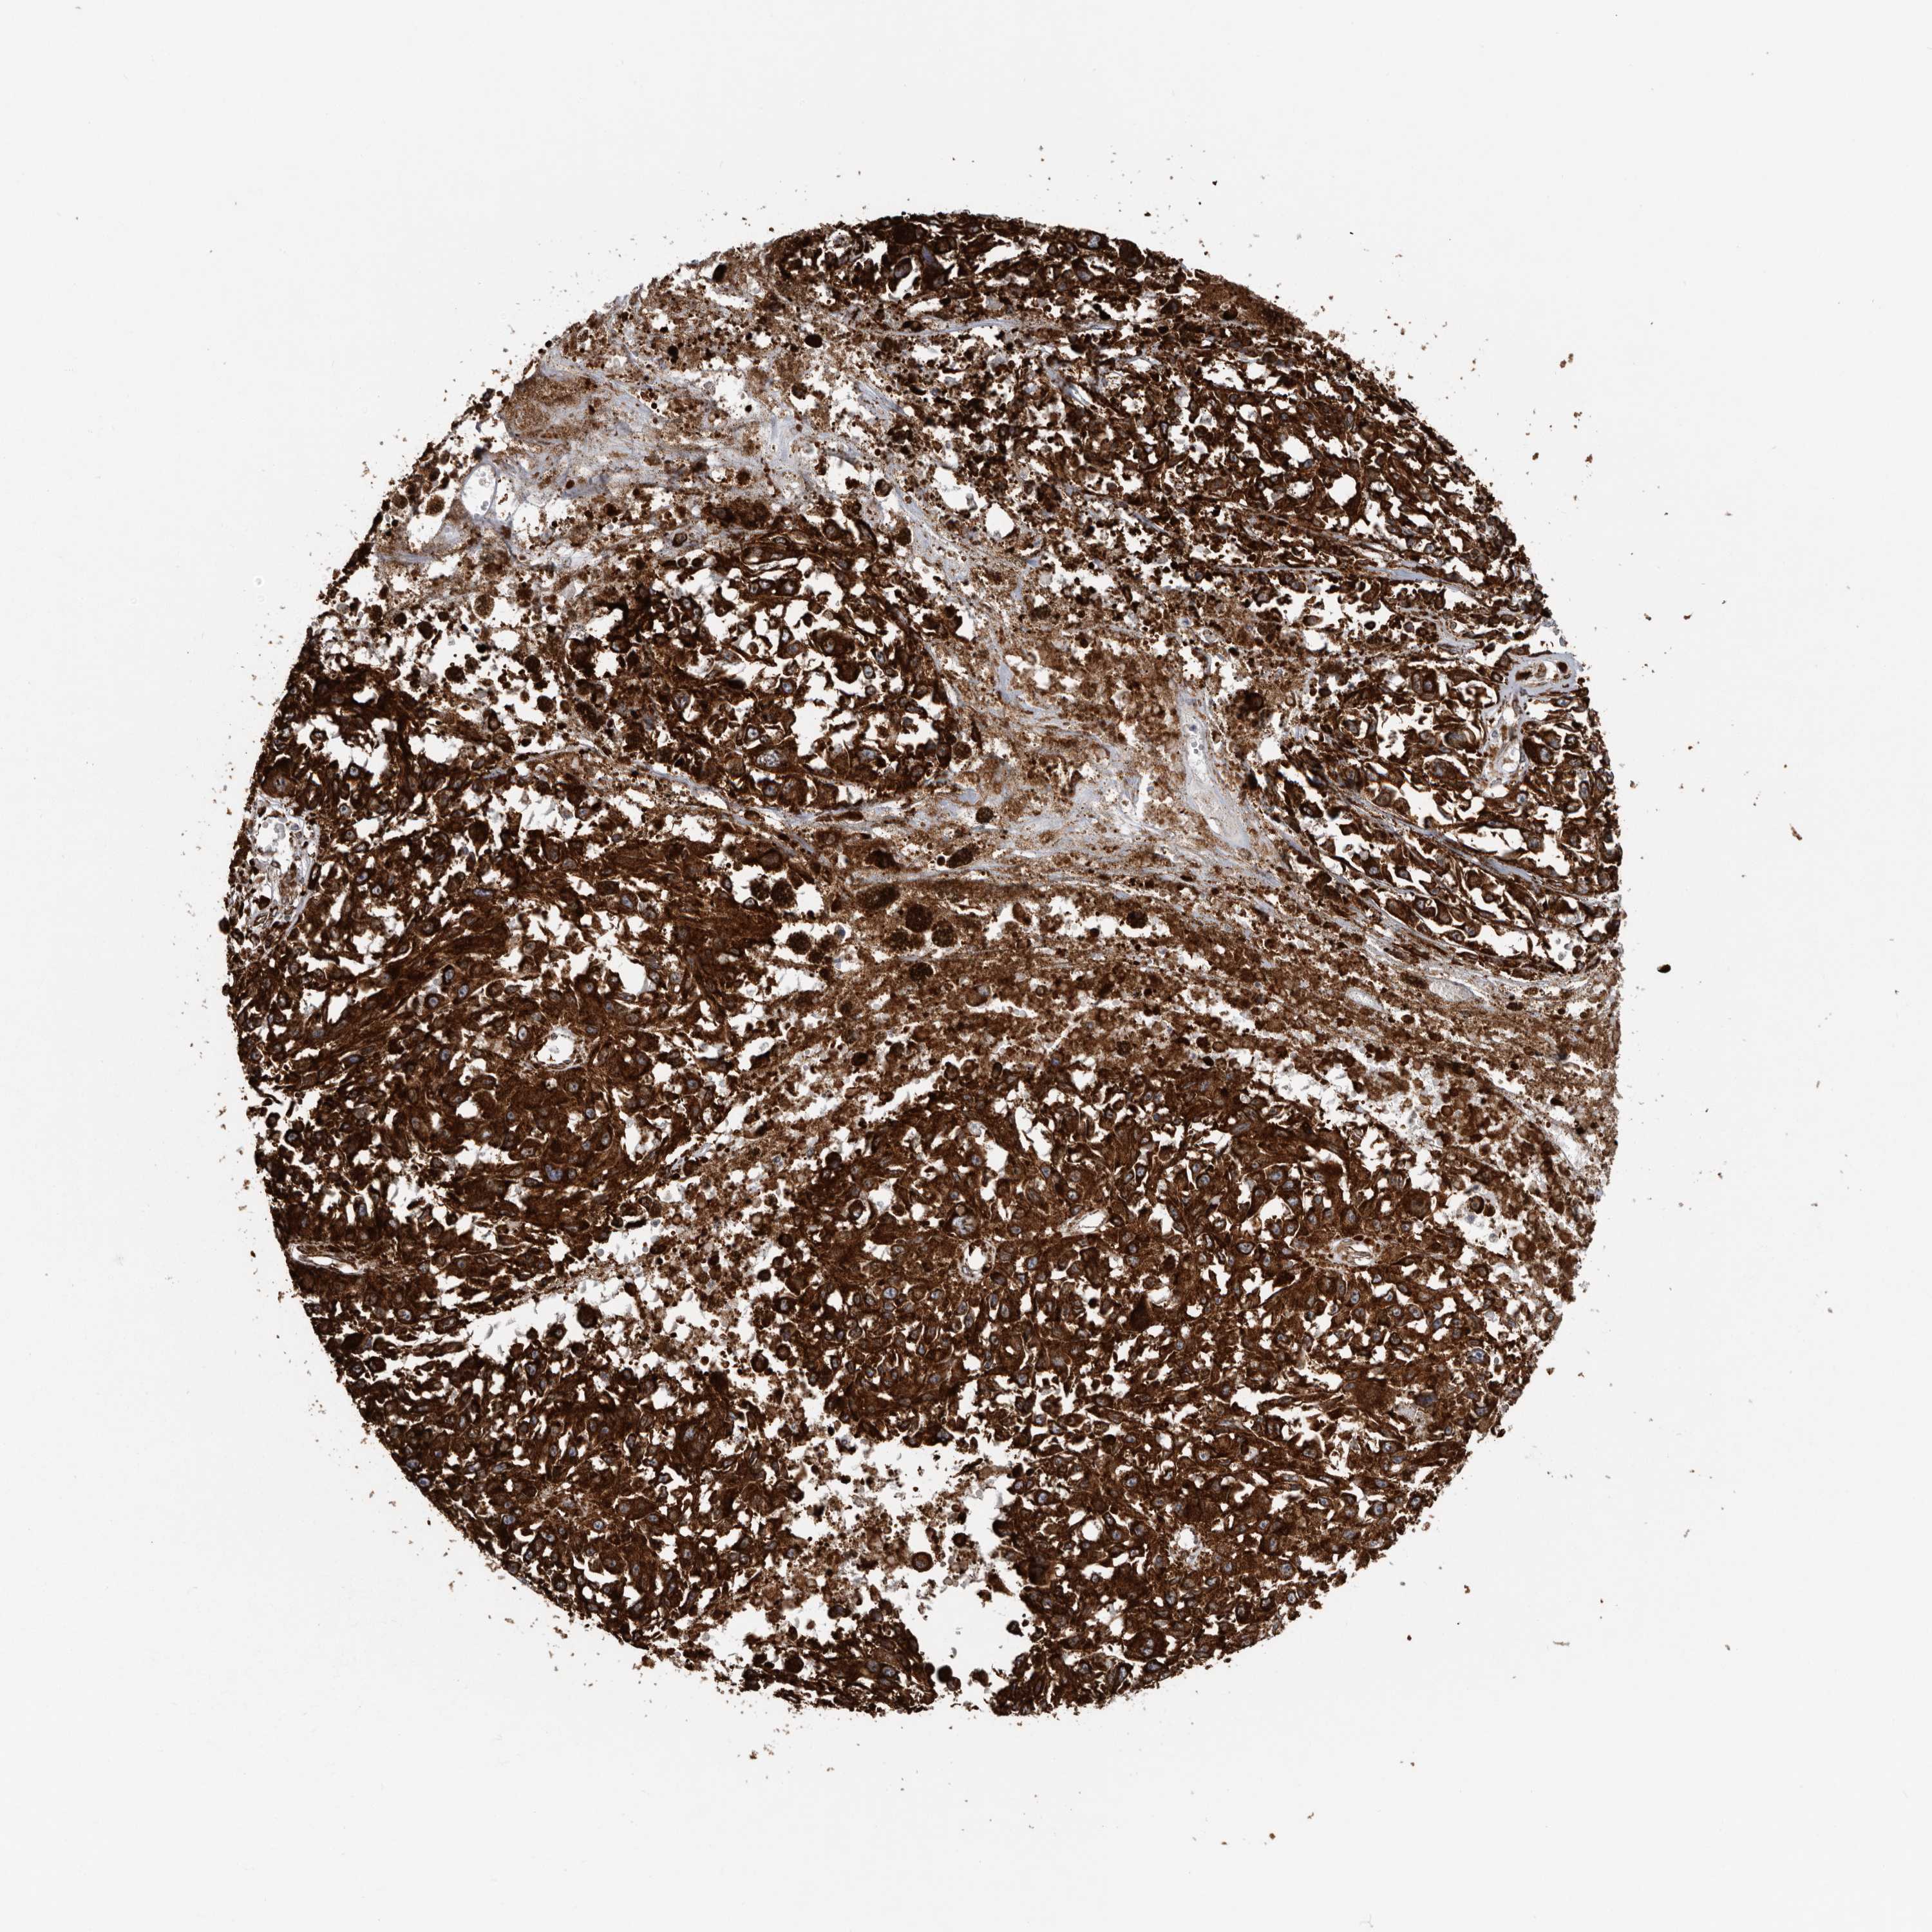

MELANOMA - Protein expressioni

A mouse-over function shows sample information and annotation data. Click on an image to view it in a full screen mode. Samples can be filtered based on level of antibody staining by selecting one or several of the following categories: high, medium, low and not detected. The assay and annotation is described here.

Note that samples used for immunohistochemistry by the Human Protein Atlas do not correspond to samples in the TCGA dataset.

Antibody stainingi

Antibody staining in the annotated cell types in the current human tissue is reported as not detected, low, medium, or high, based on conventional immunohistochemistry profiling in selected tissues. This score is based on the combination of the staining intensity and fraction of stained cells.

Each image is clickable and will lead to virtual microscopy that enables deeper exploration of all samples and also displays staining intensity scores, fraction scores and subcellular localization as well as patient and tissue information for each sample.

Antibody HPA028355

Antibody HPA028357

Staining

High

Medium

Low

Not detected

Intensity

Strong

Moderate

Weak

Negative

Quantity

>75%

75%-25%

<25%

None

Location

Nuclear

Cytoplasmic/membranous

Cytoplasmic/membranous,nuclear

Malignant melanoma, NOS

Malignant melanoma, Metastatic site